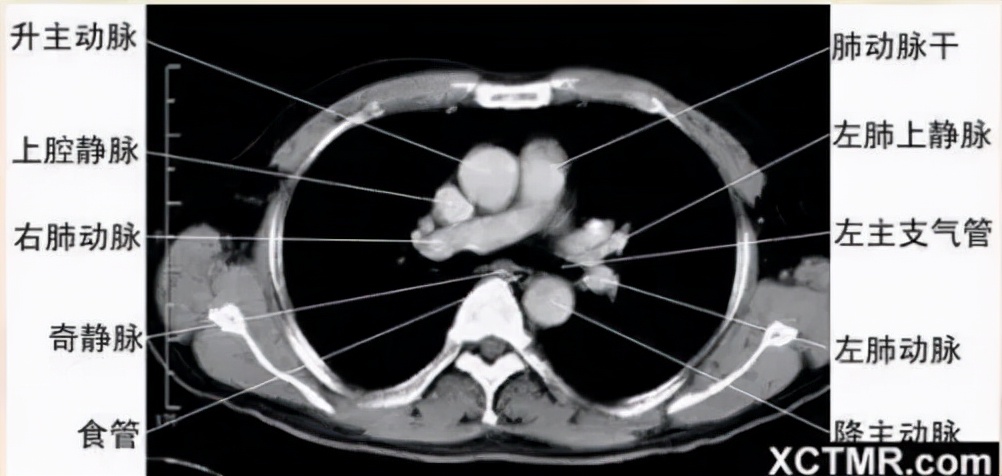

右肺动脉层面